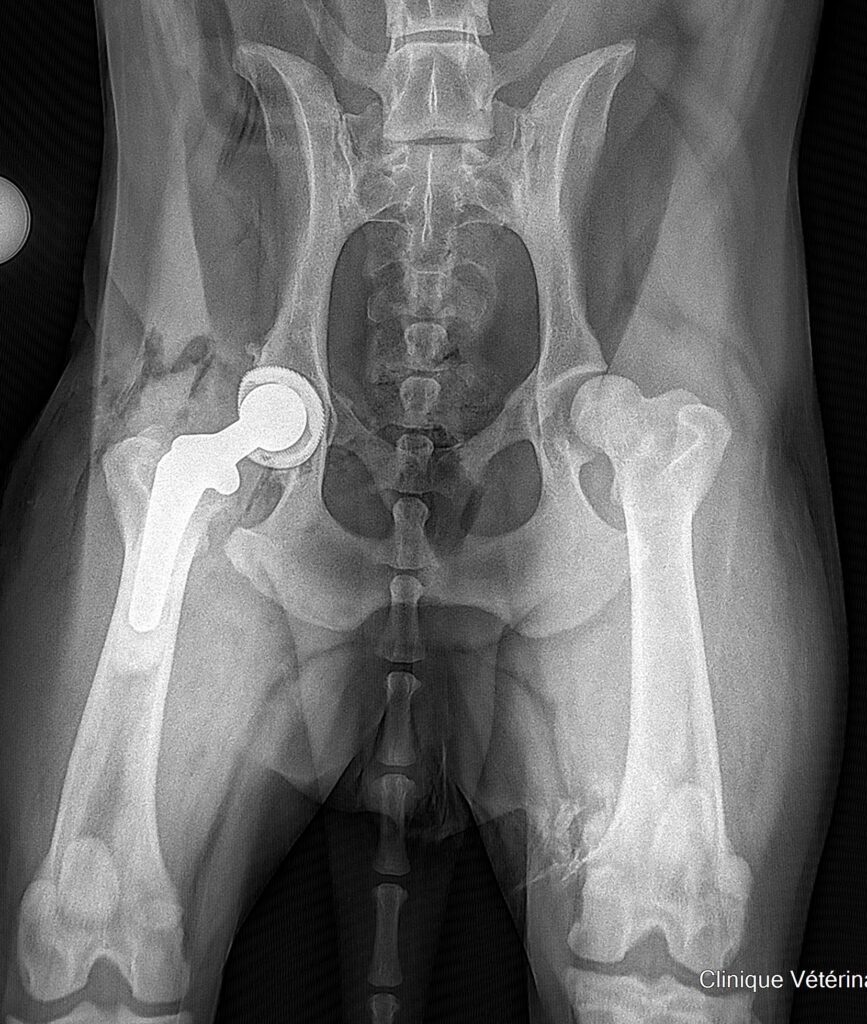

Radiographie postopératoire immédiate après pose d’une PTH. Dans ce cas, la cup a été impactée et la stem cimentée.